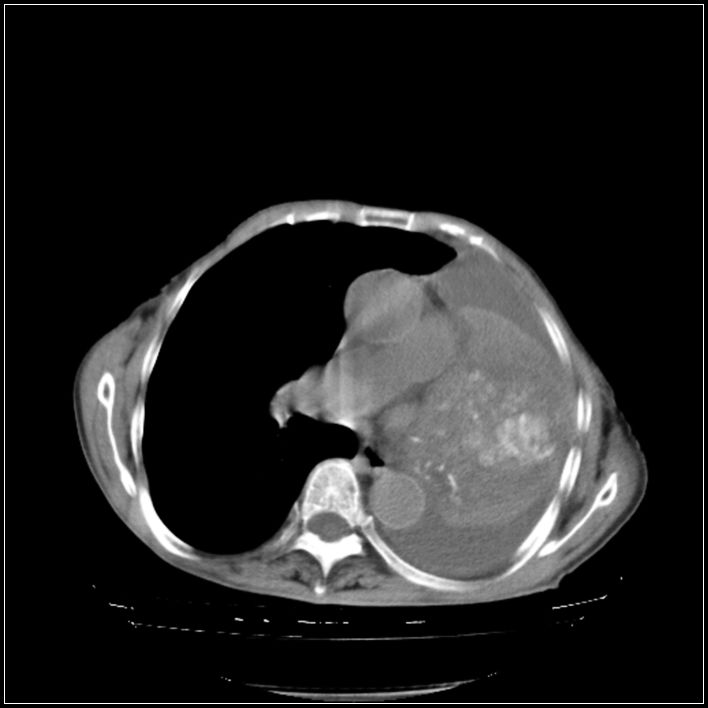

以下是引用ydx_74在2008-5-31 16:08:00的发言:[br]中心性肺癌并左侧肺不张、胸水。